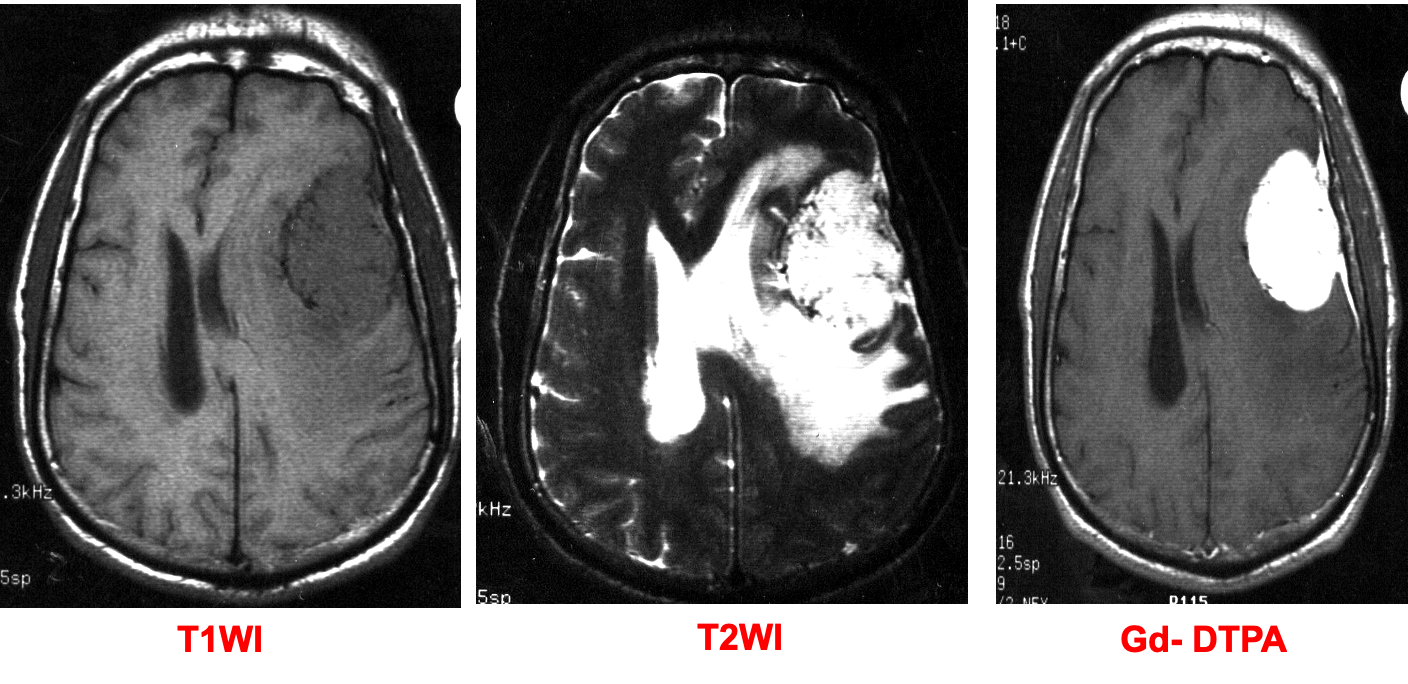

- Round, sharply demarcated space-occupying lesion with radiological features of an extra-axial tumor

- T1: isointense or hypointense

- T2: isointense or hyperintense

Contrast MRI findings

- Significant homogenous enhancement of the meningioma

- Dural tail sign.

There is an oval mass in the left parietal region, with well-defined borders, appears hypointense to grey matter on the T1 & hyperintense on T2-weighted image. There is ipsilateral ventricular compression and contralateral shift of midline structures and both ventricles associated with perifocal edema. The lesion shows homogeneous enhancement on the contrast T1-weighted image and a dural tail